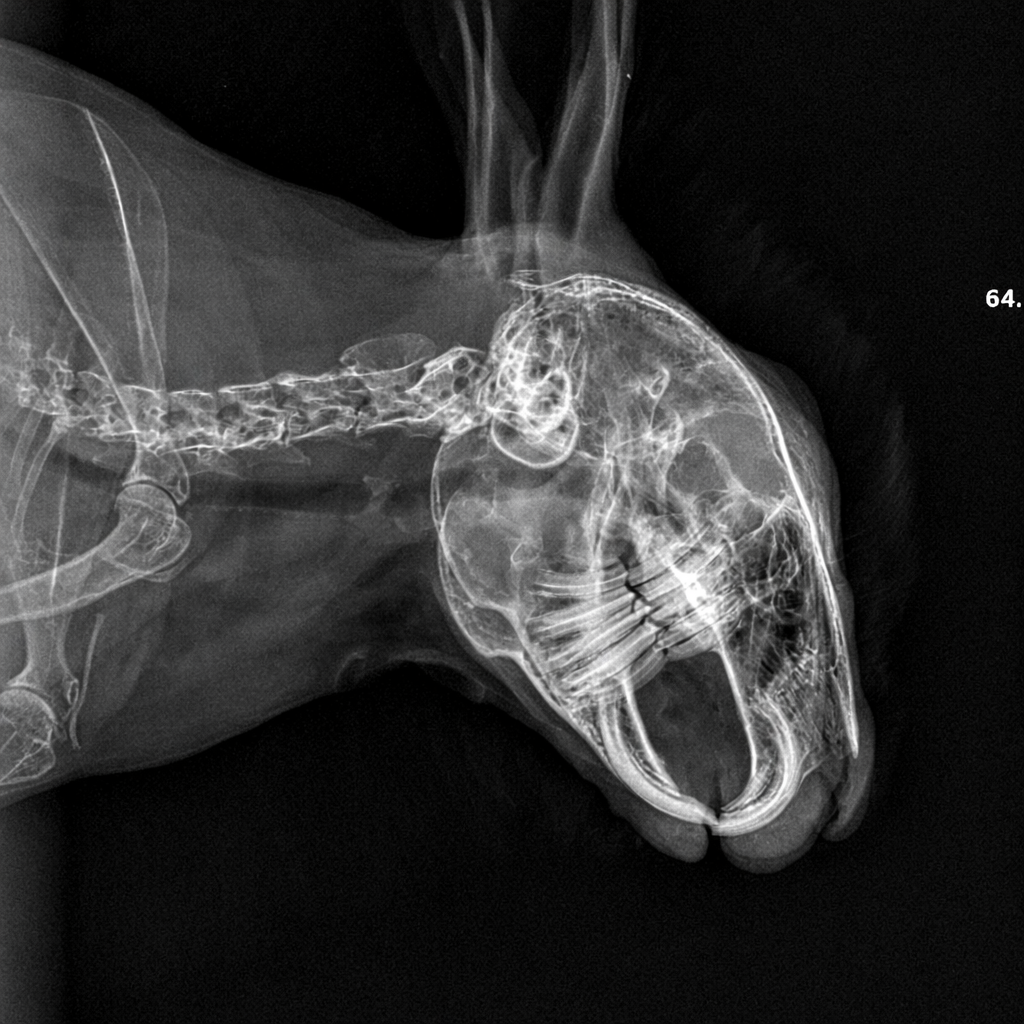

Konijnentanden groeien levenslang – tandcontrole konijn

Konijn Tanden

Konijnentanden groeien levenslang 🐰

Wist je dat konijnentanden blijven doorgroeien? Ontdek waarom tandcontrole essentieel is en welke signalen je niet mag missen.